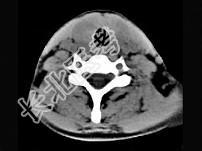

- 单项选择题40岁,女性患者, 双侧甲状腺肿大,CT扫描如图所示, 请选择最佳答案 ( )

A、弥漫性甲状腺肿

B、甲状腺癌

C、甲状腺炎(桥本)

D、亚急性甲状腺炎

E、甲状腺瘤